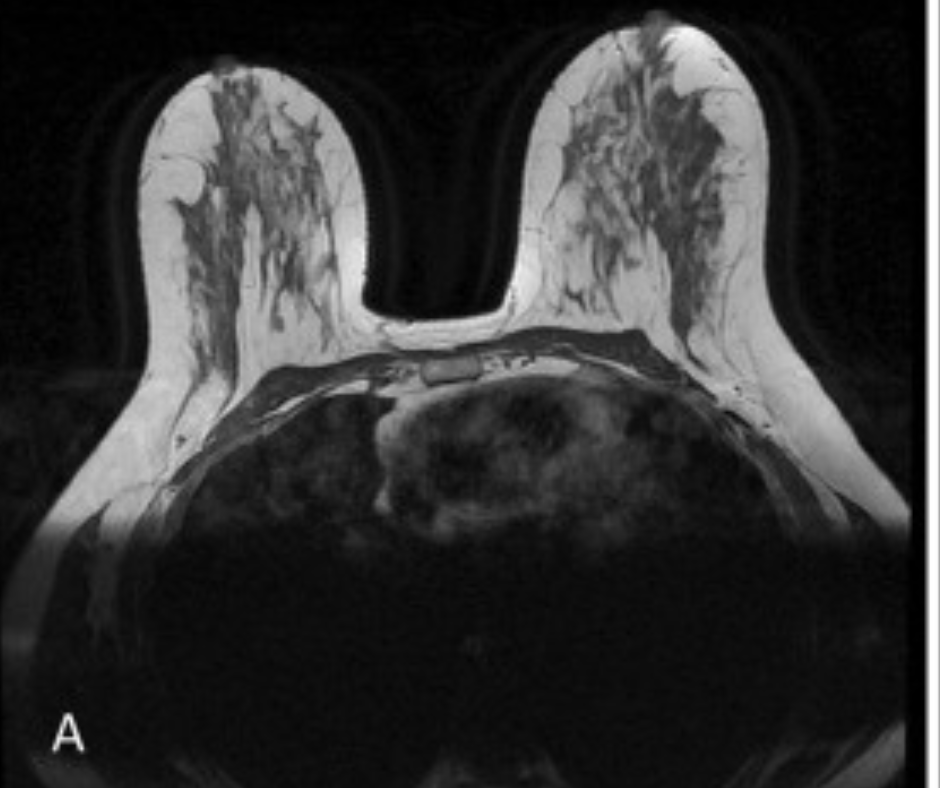

In a recent lecture at the Radiological Society of North America (RSNA) conference, Wendy DeMartini, MD, discussed a variety of preliminary proposed changes to the Breast Imaging Reporting and Data System (BI-RADS) for breast magnetic resonance imaging (MRI) examinations.